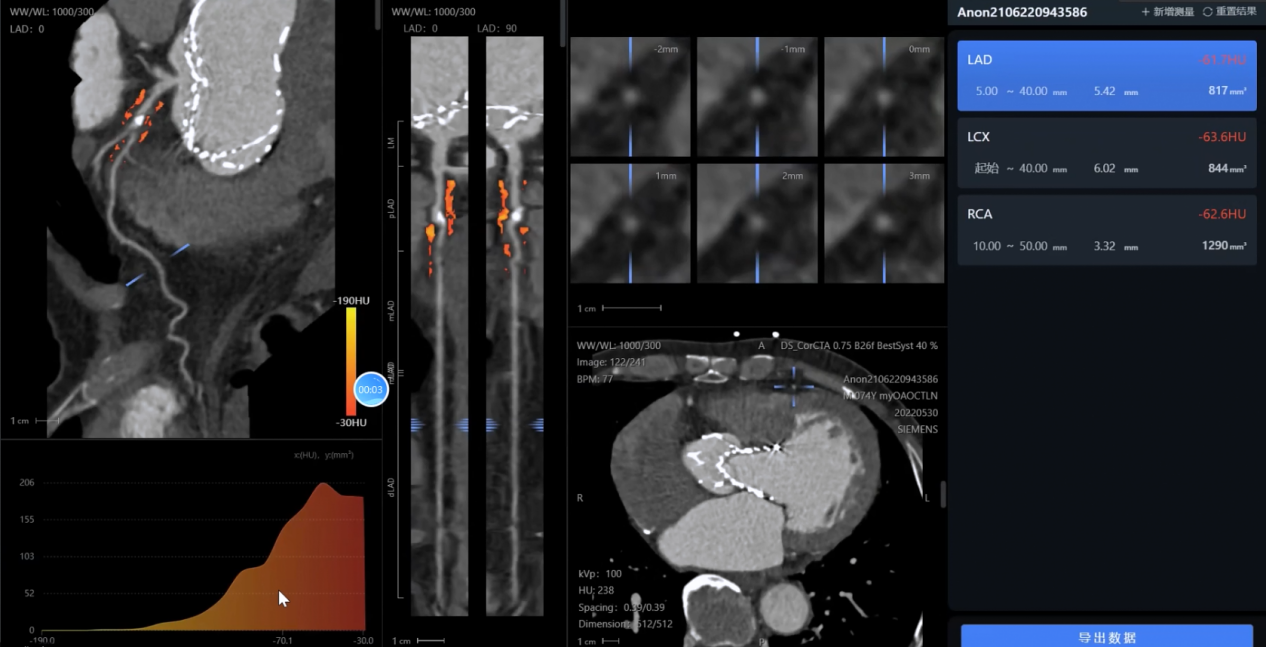

影像智能分析:對CTA、MRA等多模態(tài)影像進行自動處理和病變識別

影像分析方面:系統(tǒng)能夠自動處理心血管CTA、腦血管MRA、外周血管超聲等多模態(tài)影像數(shù)據(jù),精準識別斑塊性質、狹窄程度和病變范圍,生成結構化報告。